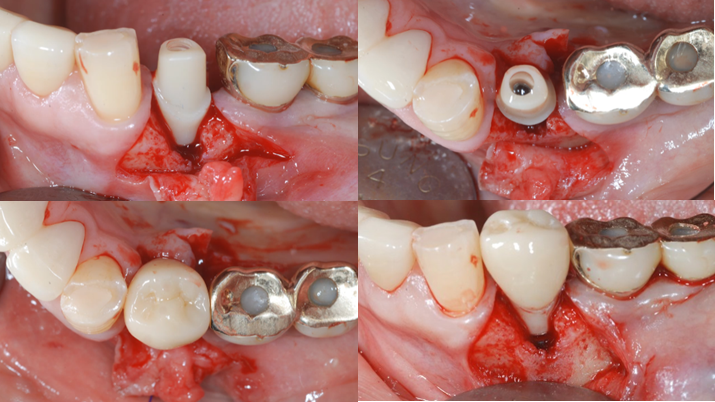

Clinical case: EImmediate implant placement & loading of #35 extraction socket with defect

- Courtesy of Dr. Kwang Bum Park, Korea -

Keywords

Dr. Kwang Bum Park, immediate loading, digital guided surgery, digital ONE-DAY implant, maxillary anterior, #21, guided surgery, immediate loading, AnyRidge, R2GATE, Mega ISQ, MEG Torq, R2GATE Full Surgical Kit

Products:

implant system, R2GATE Guide, R2GATE surgical kit (AnyRidge), Mega ISQ, Mega-Oss

“ One implant /One tooth/ One hour step-by-step

+ associated connective graft ”